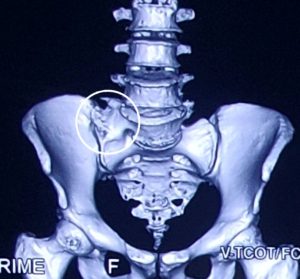

বার্টোলোটি সিন্ড্রোম (Bertolotti Syndrome)

বার্টোলোটি সিন্ড্রোম (Bertolotti Syndrome) হল মেরুদণ্ডের একটি জন্মগত অবস্থা যা পিঠের নিচের অংশে ব্যথা সৃষ্টি করে। এটি এমন একটি অবস্থা যেখানে মেরুদণ্ডের সবচেয়ে নিচের অংশের কশেরুকা (L5) sacrum বা ইলিয়াম (ilium) এর সাথে অস্বাভাবিকভাবে যুক্ত হয়ে যায়। এই অস্বাভাবিক সংযোগের ফলে মেরুদণ্ডের স্বাভাবিক কার্যকারিতা ব্যাহত হয় এবং ব্যথার সৃষ্টি হয়।

বার্টোলোটি সিন্ড্রোম একটি জন্মগত ত্রুটি। এর মূল কারণ হল লাম্বোস্যাক্রাল ট্রানজিশনাল ভার্টিব্রা (Lumbosacral Transitional Vertebra – LSTV) নামক একটি অস্বাভাবিক কশেরুকার উপস্থিতি। এই LSTV একপাশে বা উভয়পাশে Sacrum এর সাথে সম্পূর্ণরূপে বা আংশিকভাবে সংযুক্ত হতে পারে। এই অস্বাভাবিক সংযোগের কারণে মেরুদণ্ডে চাপের সৃষ্টি হয়, যা ব্যথা এবং অন্যান্য সমস্যার কারণ হতে পারে।

* সিটি স্ক্যান (CT Scan) : এই পরীক্ষাগুলো মেরুদণ্ডের হাড় এর বিস্তারিত ছবি প্রদান করে, যা রোগ নির্ণয়ে আরও সাহায্য করে।